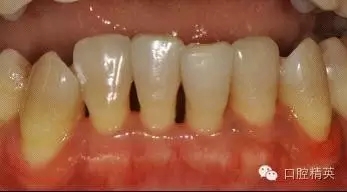

治療前:

治療后:炎癥得到控制,牙周袋已消除,松動度有所改善。